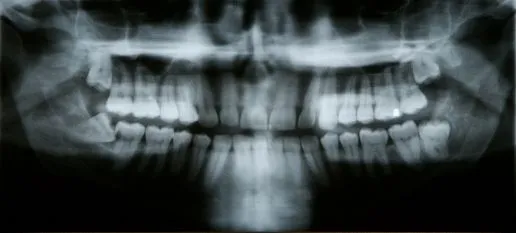

A tooth becomes impacted when there is not enough room to accommodate the space in the dental arch and growth becomes impossible. After surgery to remove an impacted tooth, mild discomfort and some swelling is expected. This is part of the process and should not alarm you. You may use cold compresses to alleviate the swelling. In addition, your doctor will prescribe pain medication, which should be taken as directed. Patients are also advised to favor the extraction area and modify their diet for a few days to allow for healing.